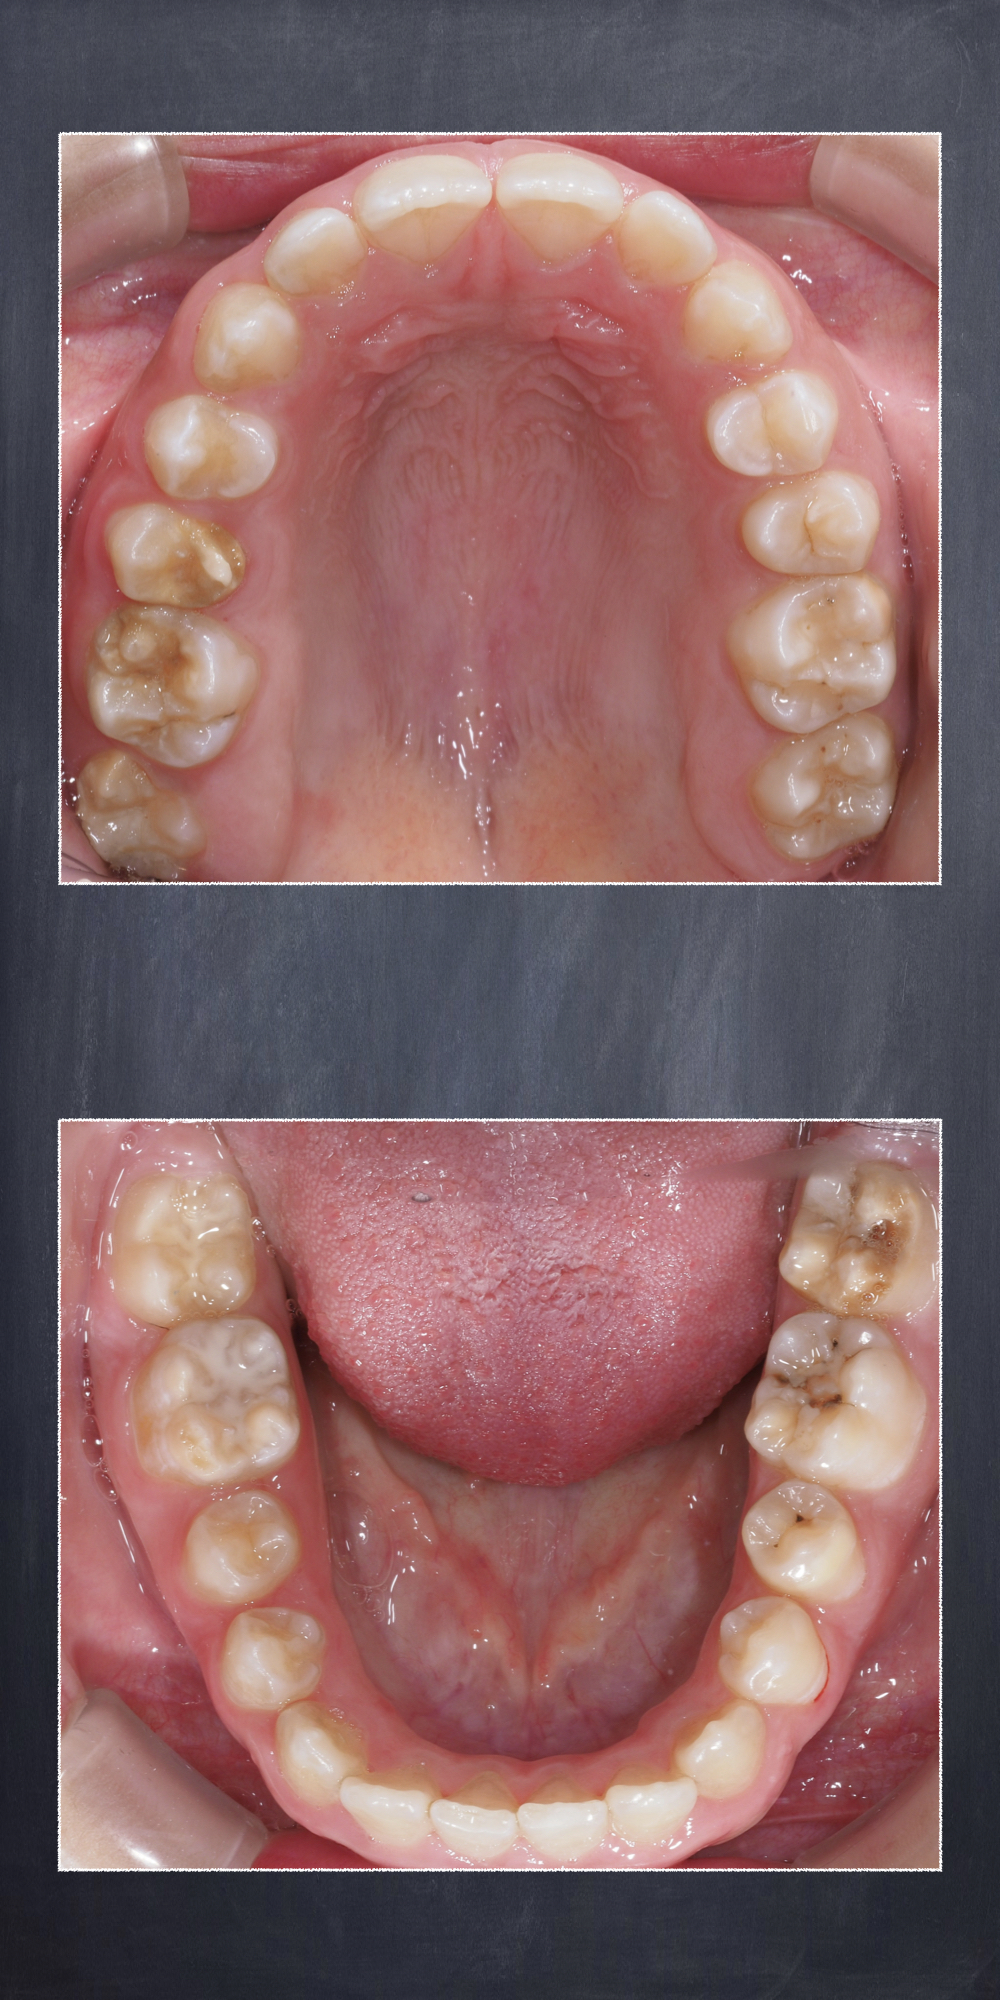

I denti maggiormente colpiti da MIH nei bambini sono i primi molari permanenti (da 1 a 4 denti) e gli incisivi permanenti (da 1 a 8 denti), ma possono essere coinvolti anche altri elementi dentari.

Le macchie variano dal bianco opaco al giallo-marrone a seconda della porosità dello smalto e sono sempre più scure e su zone di dente sempre più ampie in funzione della gravità della patologia. Spesso si tratta di un problema puramente estetico a livello dei denti frontali mentre quadri clinici più importanti si possono riscontrare nei denti posteriori dove a volte i denti sono completamente malformati che devono essere valutati da un dentista.

Nei casi più gravi, una delle possibili complicanze è quella di andare incontro ad un vero e proprio crollo strutturale del dente che, essendo più debole e più soggetto a carie, non riesce a resistere alle importanti forze sviluppate durante la masticazione.